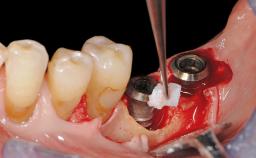

Resective Surgical Treatment of Peri-Implantitis Including Implantoplasty

In this case, Myroslav Solonko, Ignacio Sanz Sánchez and Mariano Sanz present a treatment that aims to eliminate exposed implant threads by modifying the implant surface, converting a moderately-rough surface into a smooth surface.

A 63-year-old male patient was referred to the post-graduate periodontal clinic of the Complutense University of Madrid for the treatment of peri-implantitis. According to the patient’s record, all his maxillary teeth had been extracted ten years previously due to severe periodontitis, and a full-mouth implant-supported restoration on eight implants was placed. No supportive periodontal therapy was provided apart from occasional check-ups by the restorative dentist.